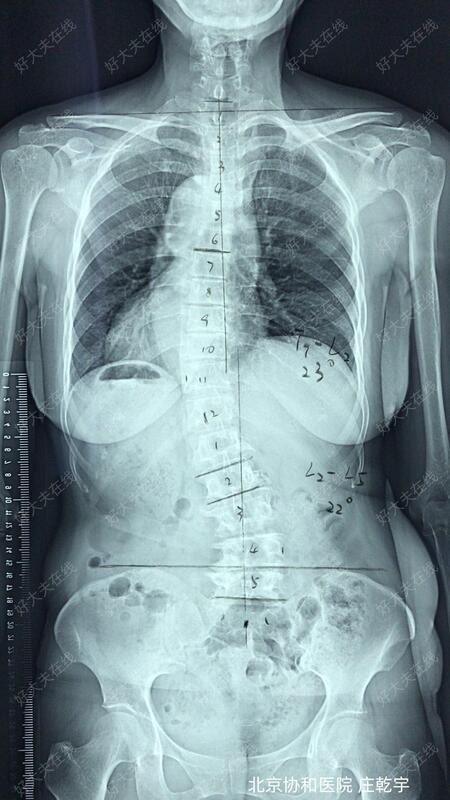

术前X片可见患者退变性腰椎侧弯,L4腰椎滑脱;

术前设计行L3-5椎管减压、L4滑脱复位、L2-5固定融合;通过腰椎相对短节段固定,在解除椎管现在压迫的同时适度矫正脊柱侧弯,尽量保留腰椎活动功能,便于老年人生活及日常活动所需。

患者手术过程顺利,完全按照手术方案完成。通过一次手术解决了患者的腰椎管狭窄、腰椎侧弯和腰椎滑脱;虽然患者存在韧带骨化,硬膜压迫明显,但通过精细操作未出现脑脊液漏;术后患者腰痛及间歇性跛行的症状明显缓解,侧弯导致的外观异常和躯干偏移也明显矫正;术后X片可见腰椎侧弯及腰椎滑脱均得到满意的矫正。